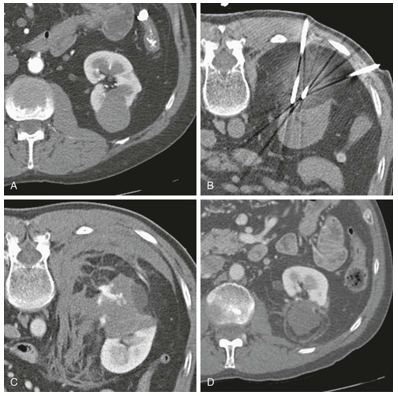

Cắt lớp vi tính

CT được sử dụng rộng rãi cả trong chẩn đoán và phân giai đoạn ung thư biểu mô tế bào thận. Trên CT không tiêm thuốc cản quang,tổn thương thường có tỷ trọng mô mềm, dao động trong khoảng 20–70 đơn vị Hounsfield. Các khối u lớn thường có những vùng hoại tử, và khoảng 30% trường hợp có vôi hóa. Trong thì vỏ–tủy, từ 25 đến 70 giây sau tiêm thuốc cản quang, ung thư biểu mô tế bào thận biểu hiện mức độ ngấm thuốc thay đổi, thường thấp hơn so với vỏ thận bình thường. Các tổn thương nhỏ có thể ngấm thuốc tương đương nhu mô vỏ thận và do đó khó phát hiện.

Nhìn chung, các khối u nhỏ thường ngấm thuốc đồng nhất, trong khi các khối u lớn hơn có hình ảnh ngấm thuốc không đều do sự hiện diện của các vùng hoại tử. Phân nhóm tế bào sáng có thể cho thấy mức độ ngấm thuốc mạnh hơn rõ rệt.

Thì vỏ–tủy cũng là thì tối ưu để đánh giá giải phẫu mạch máu, bao gồm xâm lấn tĩnh mạch thận và các biến thể động mạch, đặc biệt khi đang cân nhắc phẫu thuật cắt thận bán phần. Sự phát triển của khối u vào trong lòng hệ tĩnh mạch, đặc biệt là tĩnh mạch thận, xảy ra trong khoảng 10% trường hợp (dao động 4–15%). Tiên lượng ở những bệnh nhân có xâm lấn tĩnh mạch chủ dưới xấu hơn rõ rệt so với trường hợp chỉ xâm lấn tĩnh mạch thận, do đó việc nhận diện chính xác trên CT có ý nghĩa quan trọng.

Thì nhu mô thận, từ 80 đến 180 giây sau tiêm thuốc, là thì nhạy nhất để phát hiện các vùng ngấm thuốc bất thường.

Thì bài xuất ít giá trị hơn, nhưng vẫn quan trọng trong việc đánh giá giải phẫu hệ thống đài bể thận, đặc biệt ở những bệnh nhân có khả năng là ứng viên cho phẫu thuật cắt thận bán phần.

Chẩn đoán hình ảnh theo dõi sau điều trị thường được thực hiện bằng CT, trong đó khuyến cáo chụp hai thì ổ bụng nhằm tối đa hóa khả năng phát hiện di căn tạng đặc. Ung thư biểu mô tế bào thận thường gây di căn tăng sinh mạch, được thấy rõ nhất ở thì động mạch khi chụp vùng bụng trên.